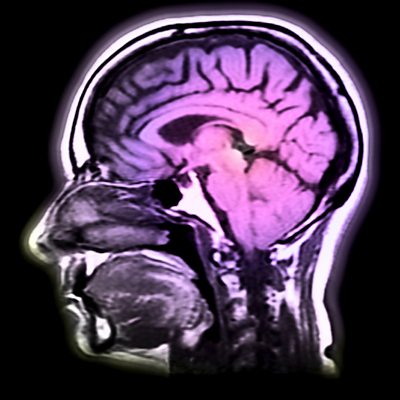

With Jane Garvey. New research has shown that far from being muddled, the brains of those aged between 40 and 60 could be in peak condition. The science writer Barbara Strauch talks to Jane about the latest findings on the middle-aged brain. A recent court case has highlighted the lack of clarity in the laws surrounding sex workers operating out of brothels. Jane discusses the implications of the case and whether this might force more women back onto the streets. Ines de la Fressange was recently voted the most stylish woman in Paris. As her guide to Parisian chic is published, she shares her style secrets with Jane. And, the artist Rose Hilton turns 80 this year. As an exhibition of her work opens in London, we visit her Cornish studio.